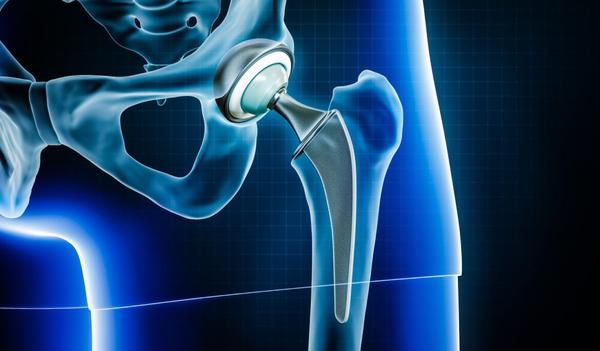

Robotic Knee Replacement Surgery

Robotic Knee Replacement Surgery by Dr. Ritesh Dang Advanced Precision. Faster Recovery. Better Results. Orthopedic Surgeon | 23+ Years of Experience | Rohini & Model Town, Delhi When knee pain becomes unbearable and limits your daily activities, knee replacement surgery is often the most effective solution. With the advancement of technology, Robotic-Assisted Knee Replacement Surgery has revolutionized the way knee replacements are performed — offering unmatched precision, alignment, and faster recovery. Dr. Ritesh Dang, a senior and trusted Orthopedic & Joint Replacement Surgeon in Delhi, is at the forefront of this innovation, offering robotic knee replacement surgery for patients seeking a more accurate, minimally invasive, and long-lasting solution. 🔹 What is Robotic Knee Replacement? Robotic Knee Replacement is not performed by a robot, but rather with the assistance of robotic technology, which helps the surgeon plan and execute the procedure with extreme precision. Using real-time 3D imaging, robotic assistance allows Dr. Ritesh Dang to: Accurately map the patient’s knee anatomy Plan the exact placement and alignment of the implant Preserve healthy bone and tissue Minimize soft tissue trauma 🔹 Benefits of Robotic-Assisted Knee Replacement: ✅ Greater Accuracy in implant positioning – improving joint function and lifespan ✅ Minimally Invasive – smaller incisions, less tissue damage ✅ Less Pain & Blood Loss post-surgery ✅ Faster Recovery Time and shorter hospital stay ✅ Reduced Risk of Complications ✅ Better Long-Term Outcomes 🔹 Who Can Benefit? Robotic knee replacement is ideal for patients suffering from: Advanced Osteoarthritis Rheumatoid Arthritis Post-traumatic arthritis Knee deformities (bow legs or knock knees) Failed previous knee surgeries Dr. Dang will assess your condition to determine if robotic-assisted surgery is right for you. 🔹 Why Choose Dr. Ritesh Dang? With over 23 years of surgical expertise and hundreds of successful knee replacements, Dr. Ritesh Dang is known for: ✔️ Expertise in robotic and conventional joint replacement techniques ✔️ Patient-first approach with clear, honest guidance ✔️ Cutting-edge technology and modern surgical infrastructure ✔️ Dedicated post-operative care and physiotherapy support ✔️ High patient satisfaction and trust across Delhi-NCR 🔹 Locations for Consultation & Surgery: 🏥 Yatharth Super Speciality Hospital 📍 4C, Institutional Area, Model Town, New Delhi – 110033 🏥 Anand Ortho Care Centre 📍 B-39, Prashant Vihar Rd, Opp. CRPF School, Sector 14, Rohini, Delhi – 110085 🔹 Book an Appointment: 🌐 Website: www.jointspecialistdelhi.com 📞 Phone: 08048035351 📧 Email: appointment@jointspecialistdelhi.com 👨‍⚕️ About Dr. Ritesh Dang: Senior Orthopedic Surgeon with 23+ years of experience Specialist in Robotic Knee Replacement, Hip Replacement & Shoulder Surgery Member of Delhi Medical Association (DMA) Trusted for delivering advanced orthopedic care with compassion and integrity